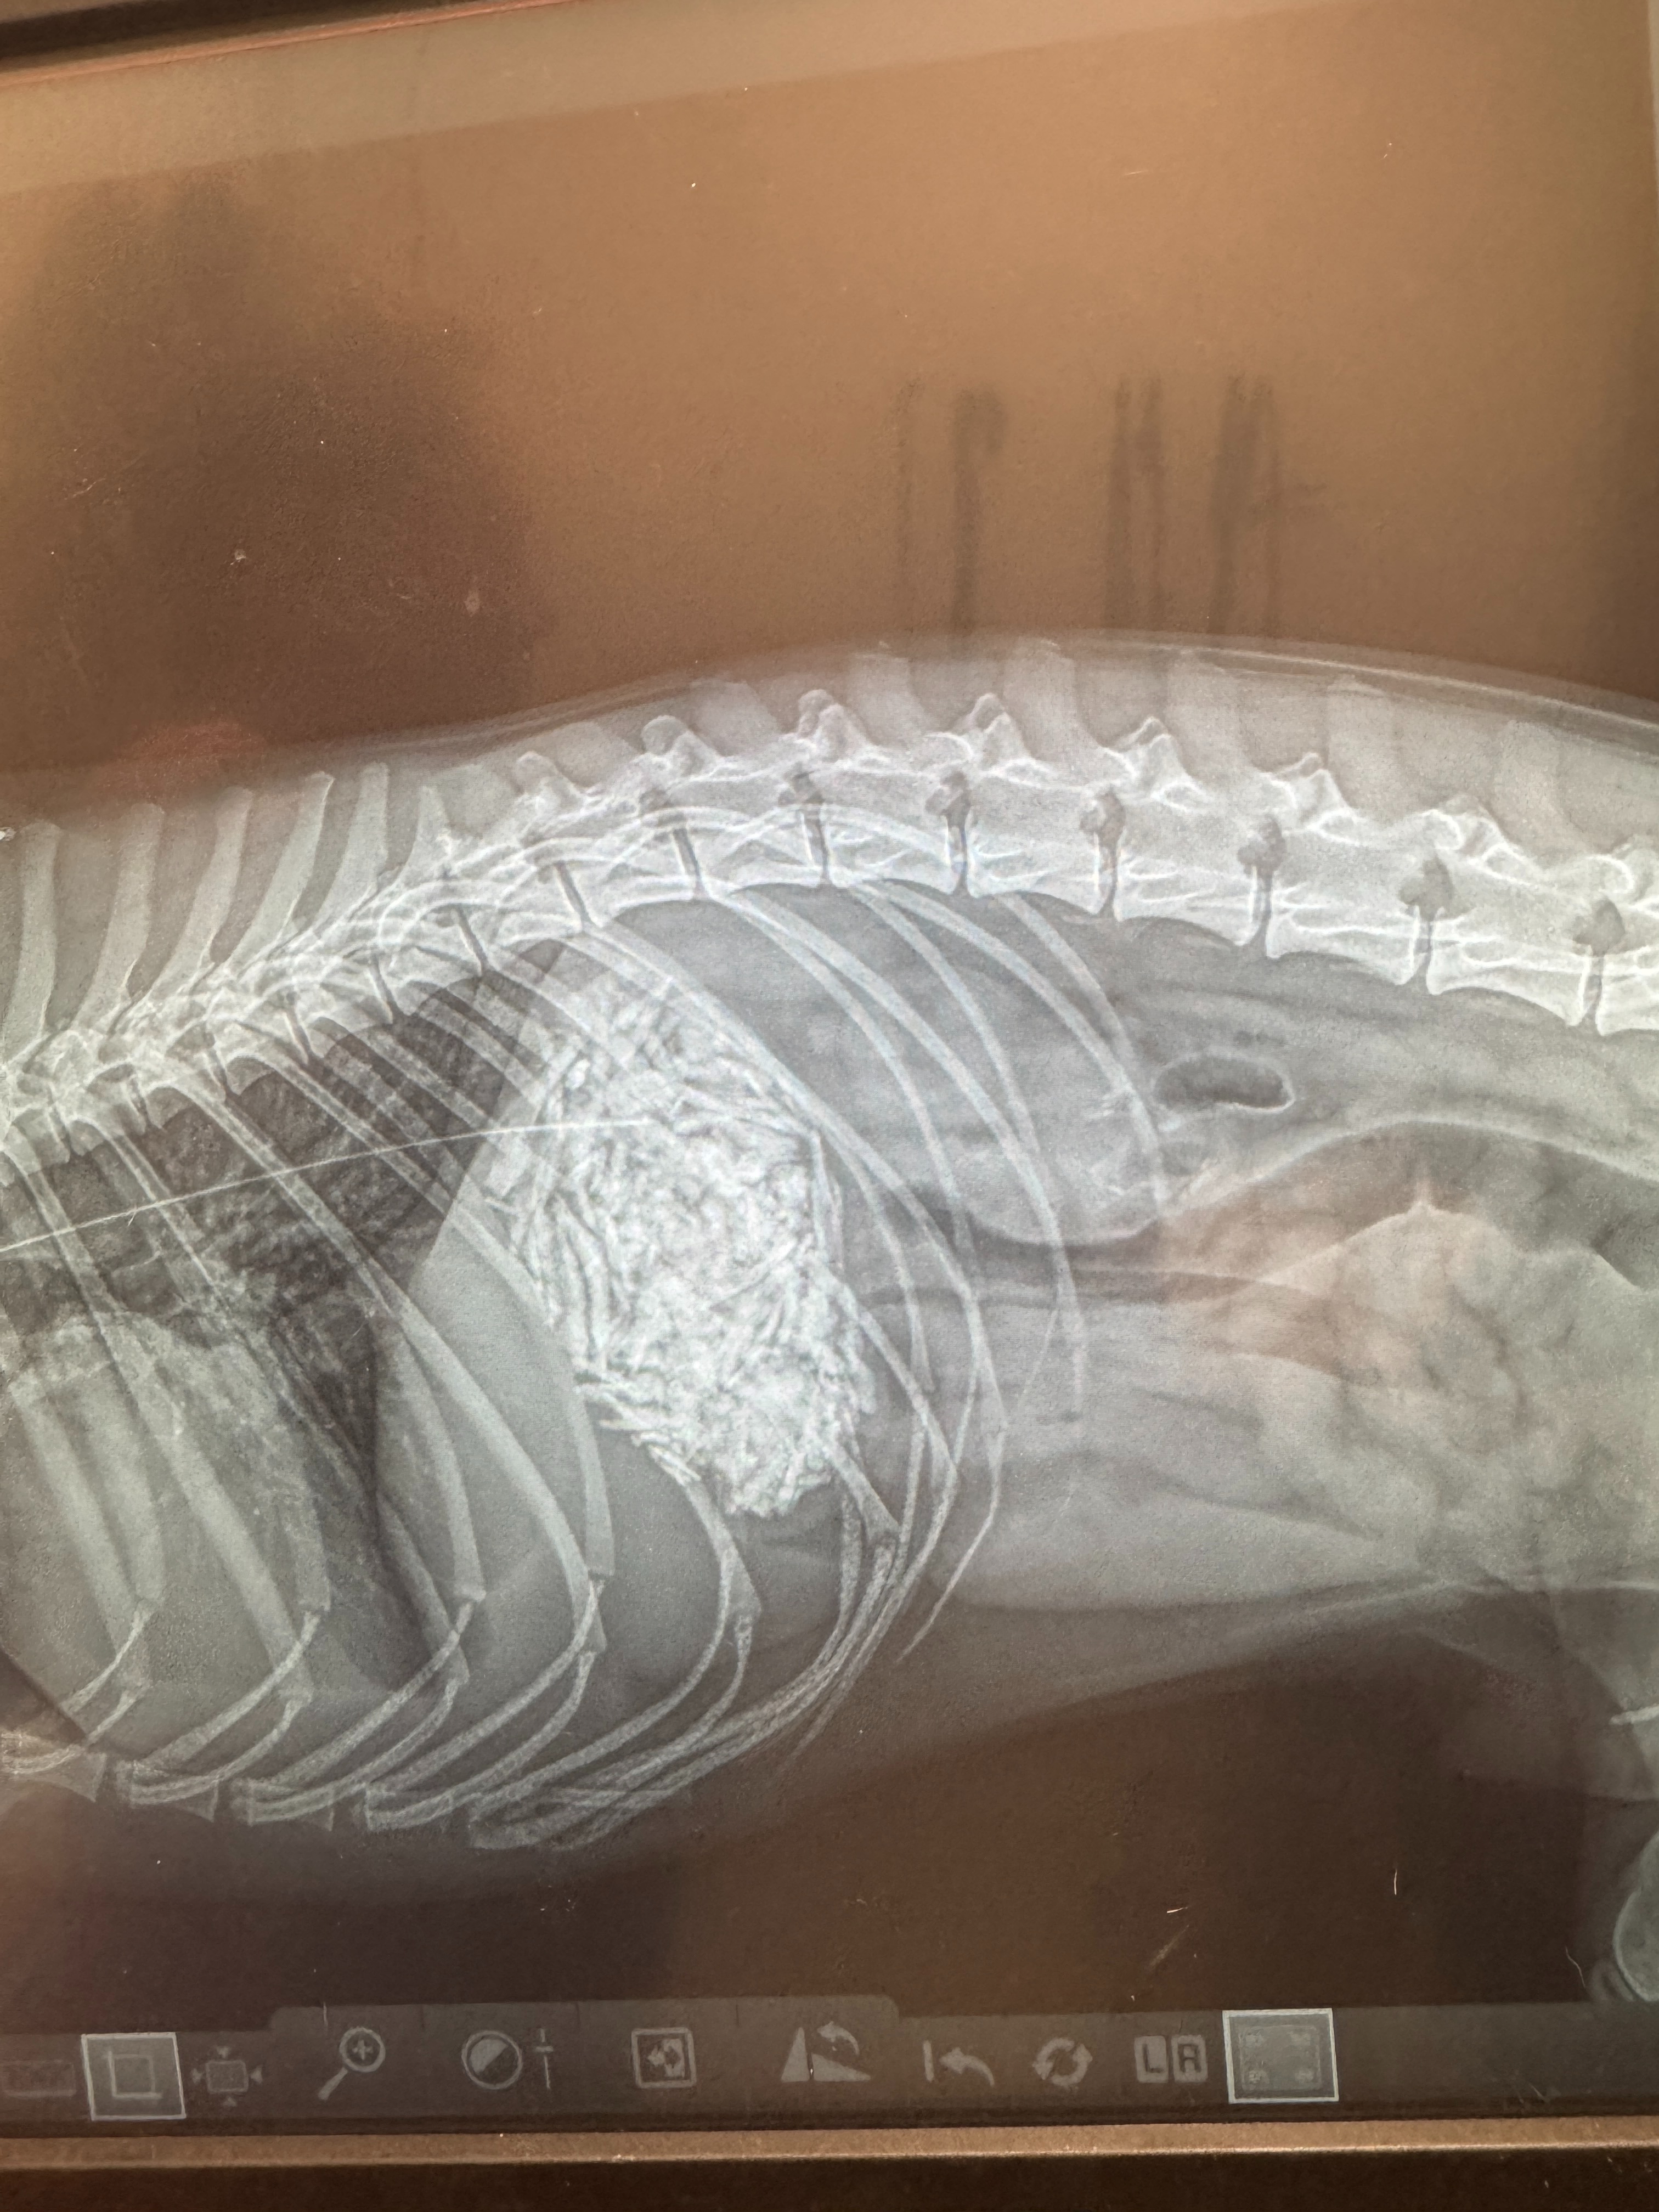

Early Saturday morning (June 29, 2025), Almond was rushed to the ER at 2:30am after we discovered he had eaten too many pork bones. It caused a dangerous blockage in his stomach, and we were faced with two options: hope that treatment and medication would work, or prepare for emergency surgery.

Unfortunately, Almond’s protein levels were too low to safely operate, so we had to wait and hope things improved. Sunday came with no change. But then on Monday — some good news. His treatment started working, and he was finally able to process food again. No surgery needed!